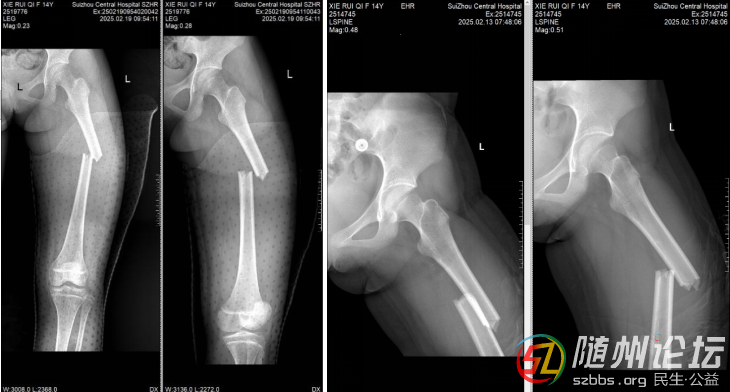

患者14歲,因意外受傷導(dǎo)致左側(cè)股骨干橫行骨折。入院時(shí)患者感左下肢劇烈疼痛,活動(dòng)受限,入院后予以制動(dòng)、理療等對(duì)癥處理,完善相關(guān)檢查檢驗(yàn),經(jīng)過科主任楊旭詳細(xì)檢查和評(píng)估,考慮到患者是青少年,骨骼仍然處于發(fā)育階段,X線片示骨骺未閉,患者家屬對(duì)預(yù)后期望值高,于是決定采用髓內(nèi)釘微創(chuàng)治療。該技術(shù)具有創(chuàng)傷小、中心固定可靠、對(duì)骨骼血運(yùn)影響小等特點(diǎn),有利于青少年骨折的愈合、早期鍛煉和骨骼的正常發(fā)育。

術(shù)前X片

術(shù)前,主管醫(yī)師羅興訓(xùn)在閱片器下測量患者左側(cè)股骨峽部為9.48mm,預(yù)計(jì)術(shù)中選擇直徑8/9/10mm三個(gè)髓內(nèi)釘型號(hào),運(yùn)用Mimics軟件進(jìn)行手術(shù)規(guī)劃設(shè)計(jì)。在充分完善各項(xiàng)術(shù)前準(zhǔn)備后,主任楊旭帶領(lǐng)團(tuán)隊(duì)?wèi){借精湛的技術(shù),精準(zhǔn)地將髓內(nèi)釘置入患者股骨骨折部位,實(shí)現(xiàn)了骨折有效的中心固定。整個(gè)手術(shù)過程順利,出血量約50ml。